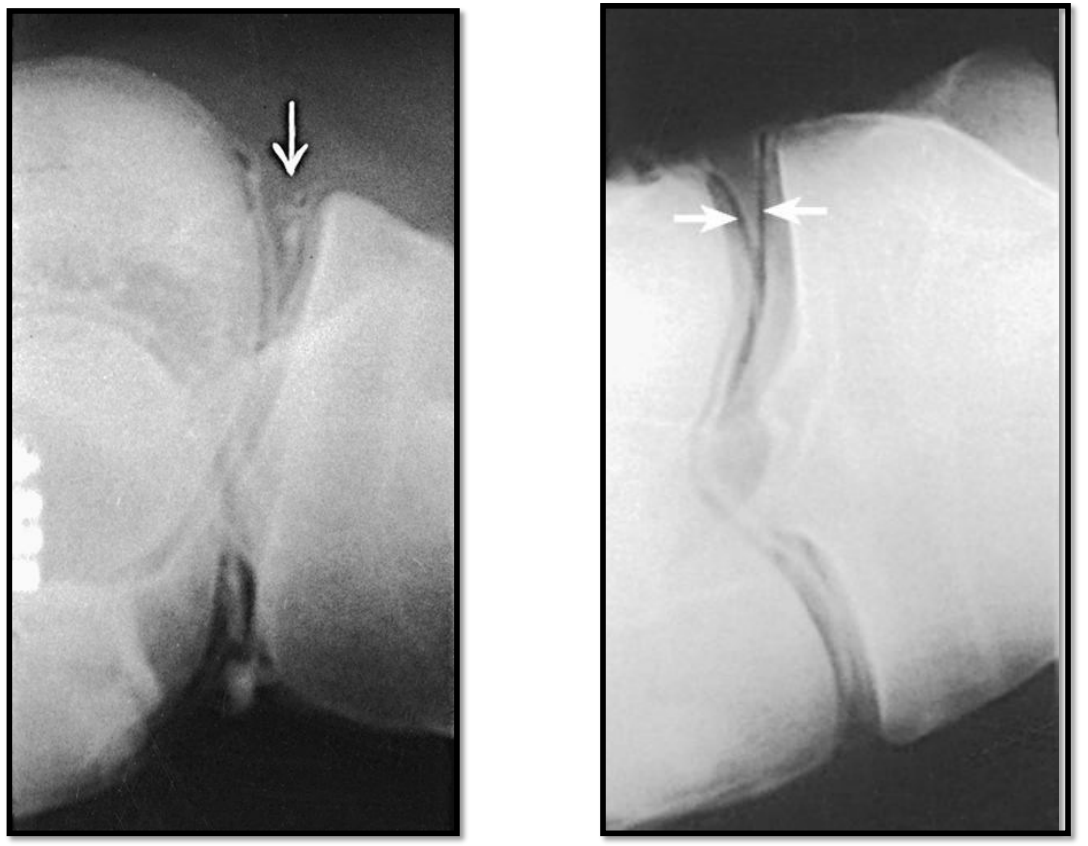

What is wrong in this arthrogram

A

• tear in meniscus allowing contrast to leak out